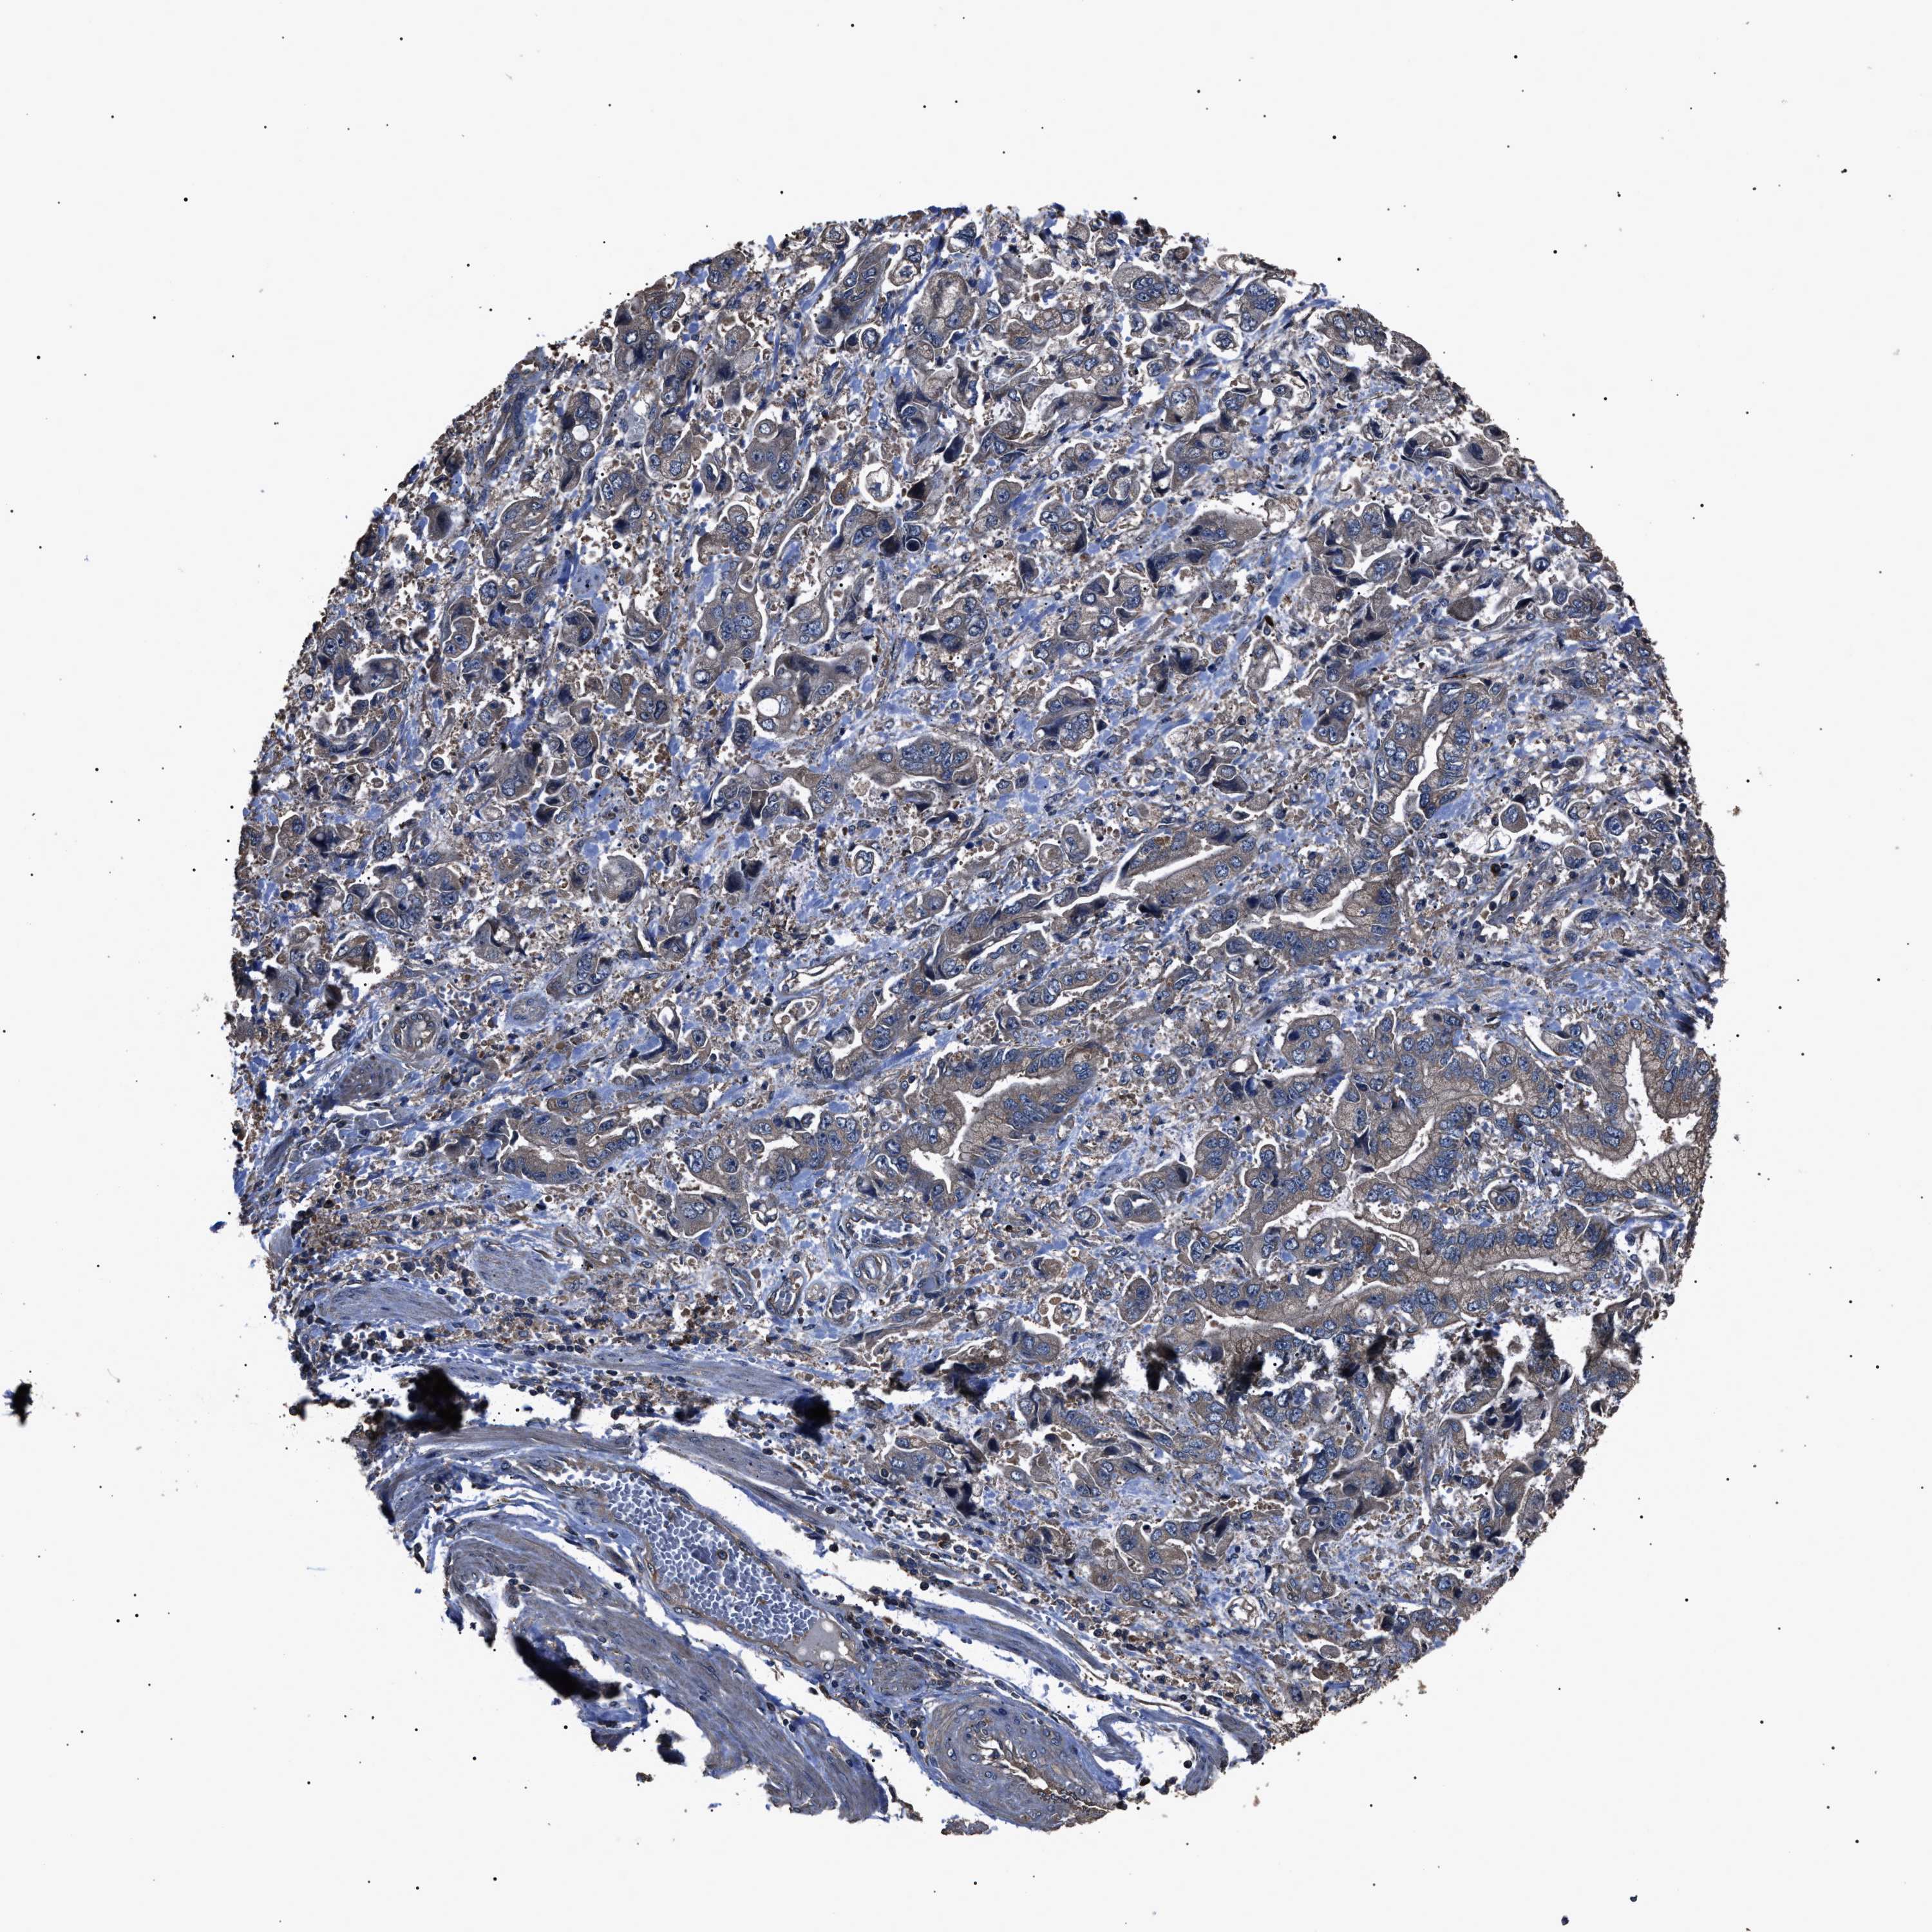

STOMACH CANCER - Protein expressioni

A mouse-over function shows sample information and annotation data. Click on an image to view it in a full screen mode. Samples can be filtered based on level of antibody staining by selecting one or several of the following categories: high, medium, low and not detected. The assay and annotation is described here.

Note that samples used for immunohistochemistry by the Human Protein Atlas do not correspond to samples in the TCGA dataset.

Antibody stainingi

Antibody staining in the annotated cell types in the current human tissue is reported as not detected, low, medium, or high, based on conventional immunohistochemistry profiling in selected tissues. This score is based on the combination of the staining intensity and fraction of stained cells.

Each image is clickable and will lead to virtual microscopy that enables deeper exploration of all samples and also displays staining intensity scores, fraction scores and subcellular localization as well as patient and tissue information for each sample.

Antibody HPA018955

Antibody HPA021123

Staining

High

Medium

Low

Not detected

Intensity

Strong

Moderate

Weak

Negative

Quantity

>75%

75%-25%

<25%

None

Location

Nuclear

Cytoplasmic/membranous

Cytoplasmic/membranous,nuclear

Adenocarcinoma, NOS